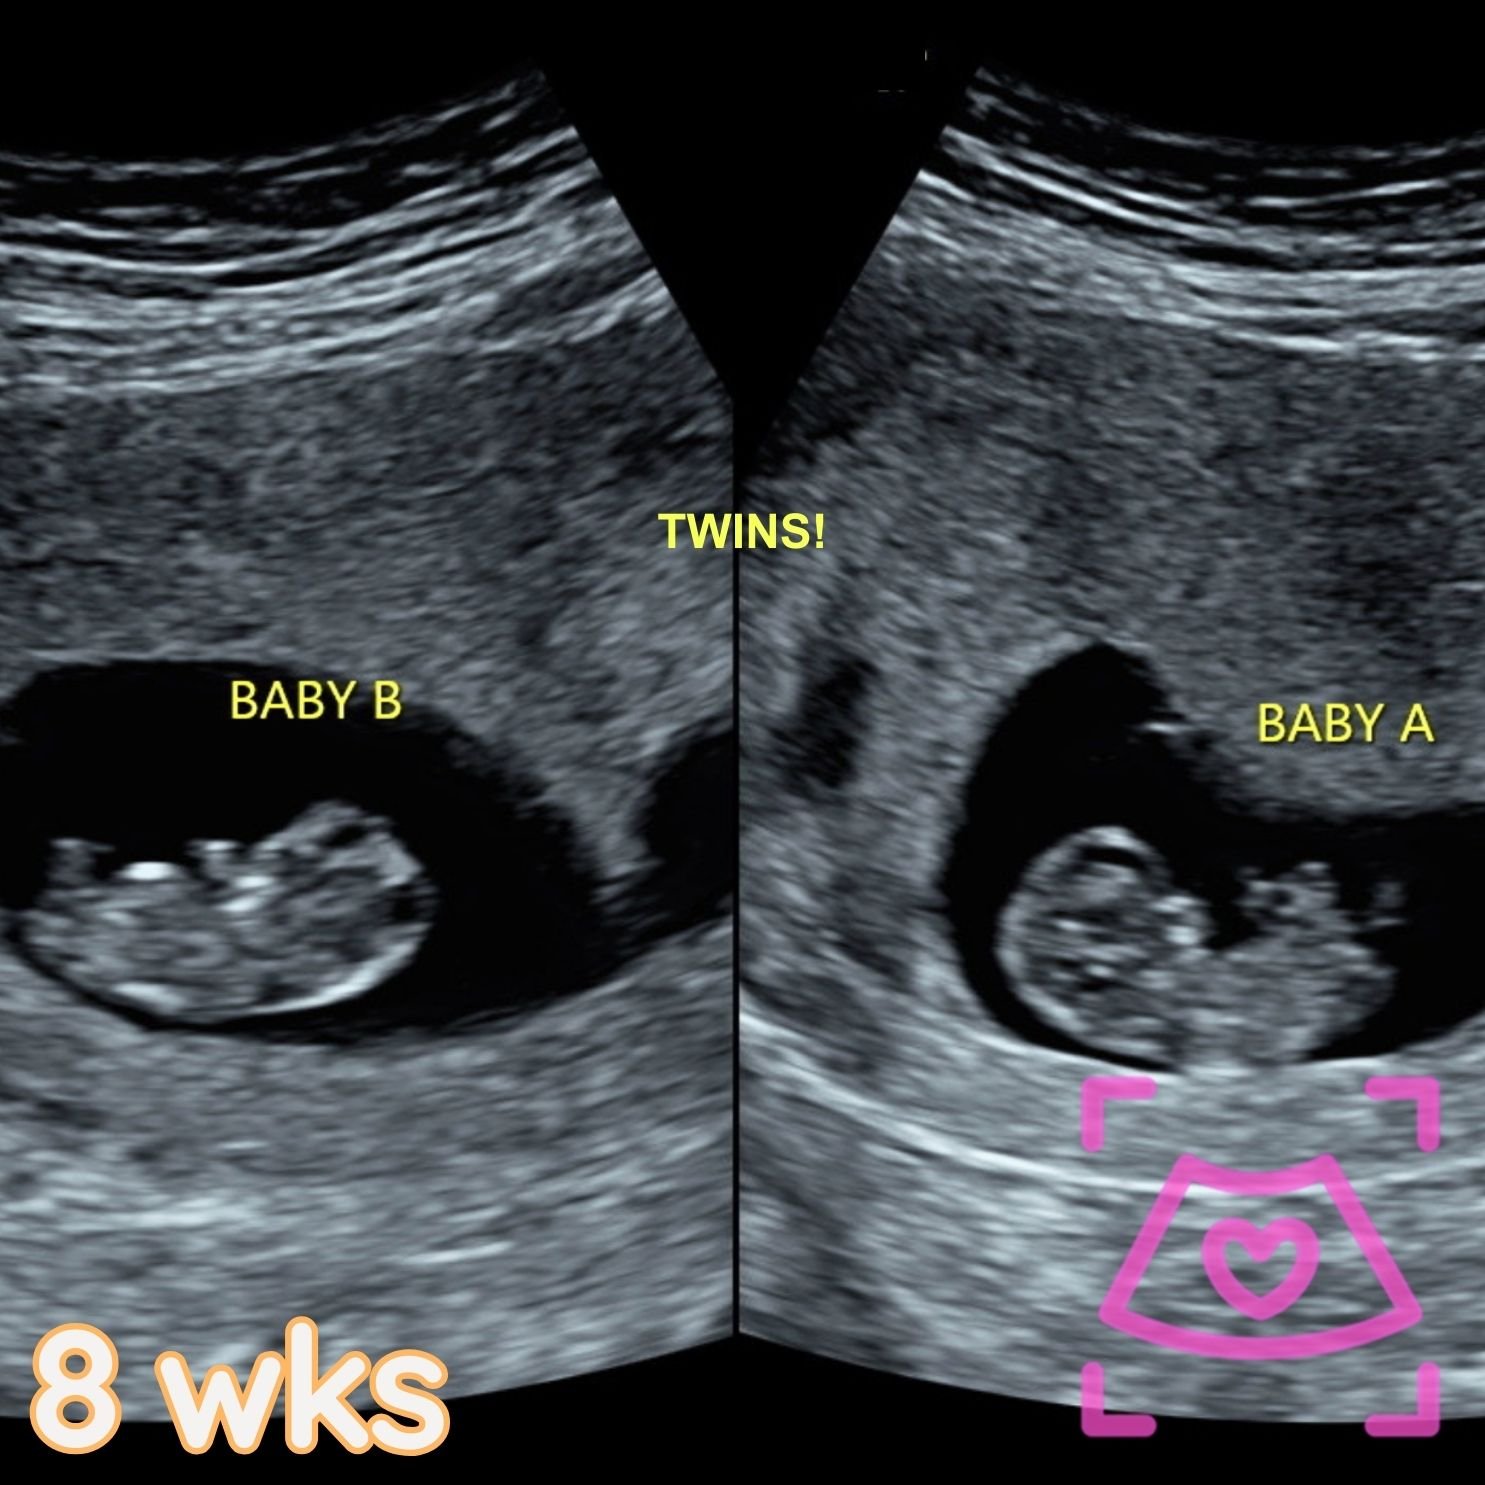

All ultrasounds at this facility are performed abdominally (on top). See examples below from 5-40 weeks! Recommended times can be found on the Services Page and when booking.

1st Trimester